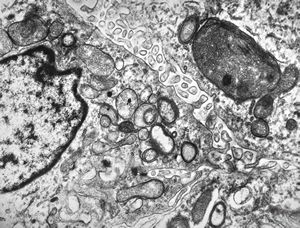

F,50y. | progressive multifocal leukoencephalopathy- viral particles in a glial cell